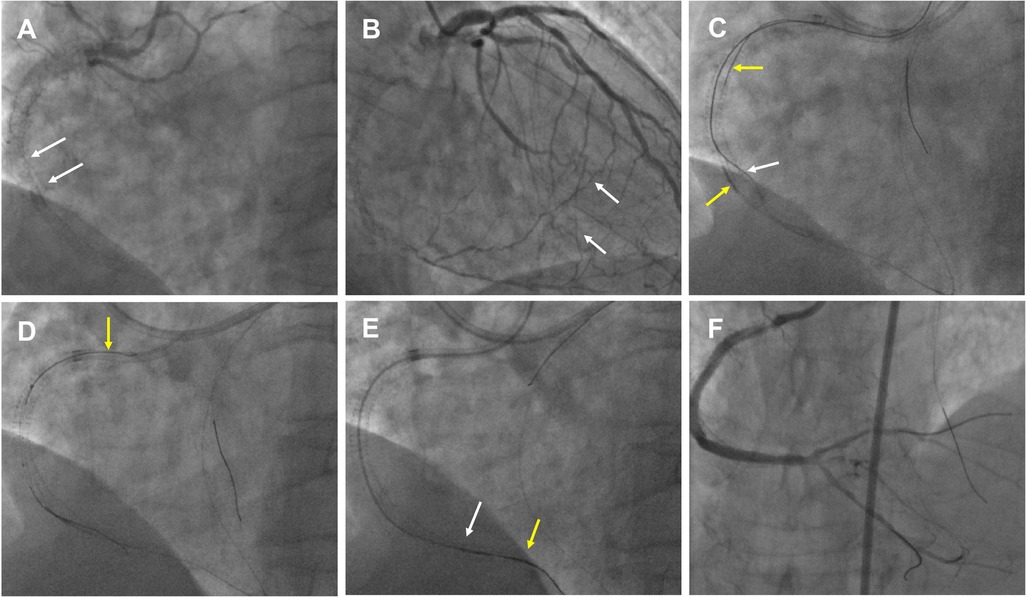

An example of the WHIH technique in a high-resistance in-stent occlusion lesion in Figure 3

Figure 3

An example of the WHIH in an in-stent high-resistance occlusion lesion. (A) RCA in-stent re-occlusion (white arrow) with deformed middle stents that had collapsed to one side. (B) RCA distal bifurcation vessels filled by contralateral septal vessels (white arrow). (C) Antegrade wire (white arrow) and retrograde wire (yellow arrow) were entered the RCA middle segment. (D) The tip-in technique performed for antegrade MC advancement over a retrograde wire (yellow arrow). (E) WHIH technique preformed when antegrade MC (white arrow) and retrograde MC (yellow arrow) uncrossable CTO lesion. (F) Excellent angiographic results were achieved after the DESs and DCB.

A 65-year-old man with a 10-year history of hemodialysis for chronic kidney failure has severe angina symptoms. Five months ago, DESs were implanted in the LAD for severe stenosis, and the in-stent CTO in the RCA was also treated. However, during the RCA CTO-PCI, the wires were positioned outside the stents in the middle segment, and the stents were dilated using 3.0/3.5 mm non-compliant balloons, achieving TIMI 3 flow in the posterior descending (PD) and posterolateral (PL) vessels. For the second PCI this time, dual CAG showed RCA in-stent re-occlusion from the proximal to just before the distal bifurcation, which was filled by contralateral vessels and featured deformed stents that had collapsed to one side (Figures 3A,B, Supplementary Video S3). Antegrade approach was first attempted, but the wires only extended into the mid-segment of the RCA and were located outside the deformed stents. Next, the retrograde Suoh3 wire crossed the septal vessel into PD vessels with Corsair MC 150. After several attempts with stiffer wires to penetrate the CTO failed, a knuckled Fielder XT-A (Asahi Intecc) wire was successfully advanced into the RCA middle segment. However, the retrograde Corsair MC was hindered at the end of the distal stent. Antegrade Fielder XT-A knuckled wire was pushed into the RCA middle segment, and after 1.5/2.0 mm balloon dilation, IVUS showed that the retrograde wire was located within the in-stent structure (Figure 3C). Subsequently, the retrograde Corsair MC was replaced by TURNPIKE150 MC, which was advanced to the RCA middle segment. After the reverse-CART technique, a new Pilot 200 wire was retrogradely manipulated into the antegrade GC (Supplementary Video S4). However, the TURNPIKE150 MC only reached the RCA 2 segment. The tip-in technique was performed to facilitate antegrade MC advancement over the retrograde wire (Figure 3D, Supplementary Video S5). Due to stent higher resistance, the antegrade MC only extended to the RCA distal stent segment, and in this dilemma, the WHIH technique was performed, and the antegrade wire was smoothly advanced into the ostium of the PD vessel while tracing along with the retrograde wire (Figure 3E, Supplementary Video S6). The final angiography showed good results with DESs and DCB (Figure 3F).